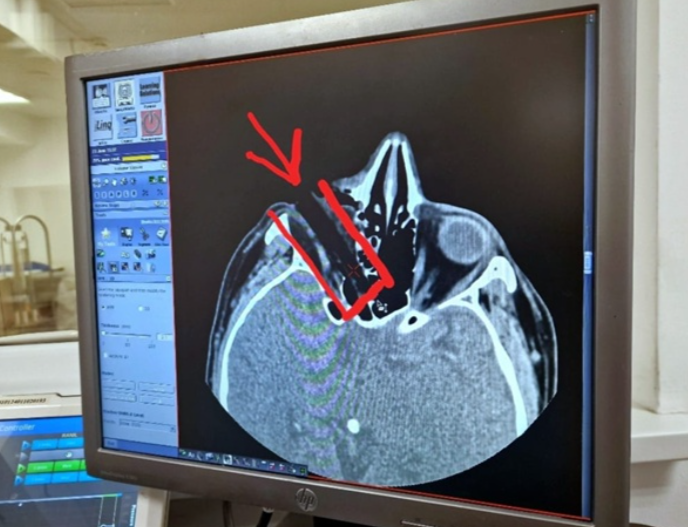

Медики диагностировали «проникающую рану глазницы с инородным телом», «смещение глазного яблока», острота зрения — 0%. Компьютерная томография показала повреждение глазного нерва и инородное тело размером 7 на 1,5 см, застрявшее в 8 мм от основания черепа. Врач-офтальмолог отметил, что глаз было не видно, а яблоко сместилось под надбровные дуги. Пациенту была проведена экстренная операция.